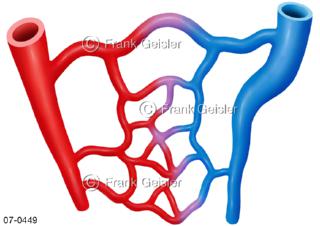

Bildergalerie Herz, Blutkreislauf

Bilder zu Herz, ein muskuläres Hohlorgan, das den menschlichen Körper durch rhythmische Kontraktionen mit Blut versorgt und dadurch die Durchblutung der Organe sichert, das Kreislaufsystem zeigt den Transport von arteriellem sowie venösem Blut durch das kardiovaskuläre System (Herz-Kreislauf-System), bestehend aus Blutgefäßen, Lymphgefäßen und dem Herz